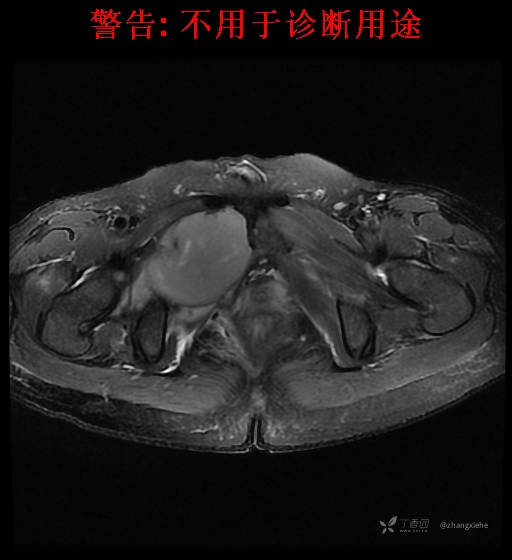

现病史:患者2022-02-07在市中医院体检发现右肺占位,胸部CT示:右肺下叶基底段见一不规则软组织密度影,增强扫描呈轻中度强化,可见血管贴边征。当时无任何不适。2022-02-24于省肿瘤医院行纤支镜检查阴性,痰检未找到癌细胞。经皮肺穿刺细胞学检查找到高度癌疑细胞,病理示:右下肺穿刺考虑神经内分泌癌。免疫组化结果:CgA(-)、CD56(-)、Syn(+)、CK广谱(-)、p40(-)、P63(少量+)、TTF-1(-)、Ki-67(+,40%)、NapsinA(-)、Calcitonin(-)、TG(-)。ECT示:全身骨扫描未见明确骨转移征象。患者出现贫血且逐渐加重、低蛋白血症,予人促红素注射液、精蛋白重组人胰岛素混合注射液、人血白蛋白对症处理,效果不明显,病情加重,右髋出现疼痛,不能行走。2022-03-04转院南大二附院进一步治疗,2022-03-20行右侧髂骨穿刺活检术,术后病理结果示:考虑软组织透明细胞肉瘤。免疫组化示:瘤细胞Vim(+)、NSE(+)、S-100(+)、SOX10弱(+)、Melan-A(+)、TFE-3部分弱(+)、CK(-)、MyoD1(-)、Desmin(-)、HMB45(-)、CD34(-)、CD68(-)、CR(-)、Ki-67约15%(+)。特殊染色示:网状纤维染色(-)、PAS(±)。

2022-03-05血常规示:血红蛋白:64g/L,生化示:白蛋白20g/L。骨髓涂片细胞学检查示:骨髓增生明显活跃,粒红比减低。粒、红、巨三系增生明显活跃。粒系伴成熟障碍。髓片浆细胞较易见,占7%。粒系增生明显活跃,核明显左移,可见巨幼样变及核浆发育不平衡。PET-CT示:1.右肺下叶软组织肿块、右侧耻骨下支及耻骨联合处骨质破坏伴软组织肿块形成,FDG代谢均异常增改,考虑恶性病变,建议病理检查;右侧髂血管旁、双侧腹股沟淋巴结反应性增生,建议随访。2.多浆膜腔(双侧胸腔、心包腔、盆腔)少量积液。3.全身骨骼FDG代谢弥漫增高,考虑骨髓反应性增生。4.大小肠条片状FDG代谢增高,考虑生理性摄取。5.右侧上颌窦面膜下囊肿,脑部FDG代谢未见明显异常。6.C7-T1层面后纵韧带钙化。患者乏力加重,卧床不起,不能承重,大小便不顺畅,转院至我院。门诊拟“1.右肺占位并右侧骨盆转移2.低蛋白血症3.中度贫血 4,血糖升高(原因待查)”收入住院。患者发病以来,无胸闷、胸痛,无呼吸困难,偶咳嗽,无咳血,饮食、睡眠欠佳,2个月之内体重减轻约10kg。

右骨盆及双下肢未见畸形,皮温正常,无浅静脉怒张,右腹股沟中点可触及一质韧肿物,大小约6cm*4cm*5cm,边界不清,固定、压痛明显,叩击痛阳性。右髋关节外旋、屈曲受限。右髋4字试验阳性,左侧阴性,双下肢直腿抬高试验阴性。感觉、运动正常,末梢血运良好,生理反射存在,病理反射未引出。